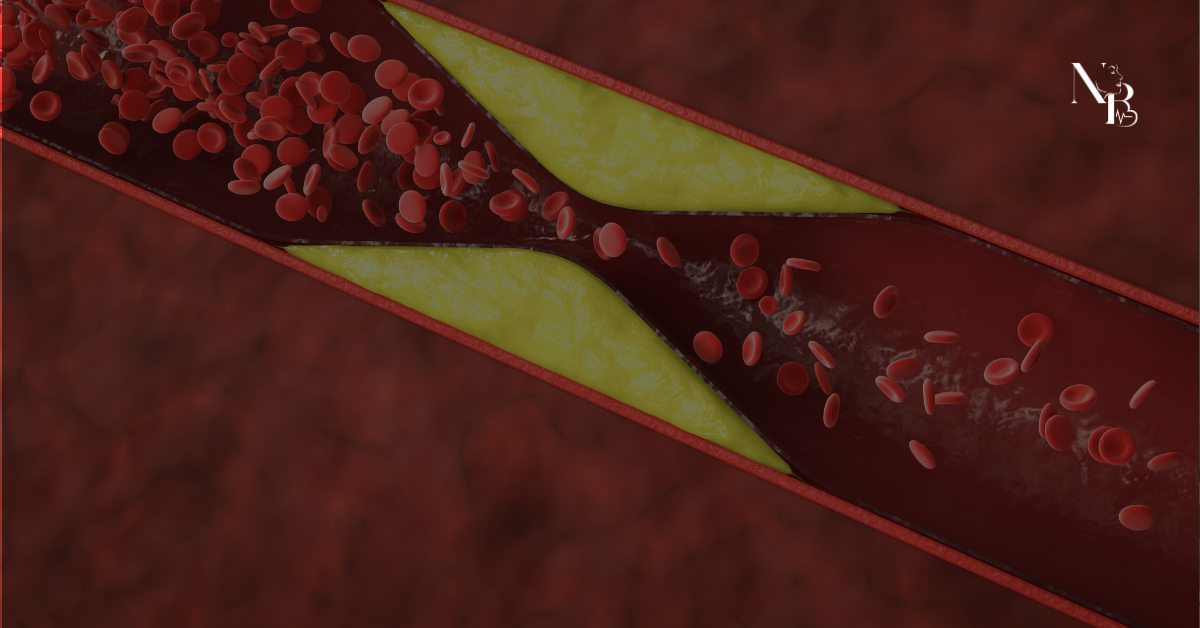

A obesidade é um importante fator de risco para o desenvolvimento de doenças cardíacas e está diretamente relacionada a alterações